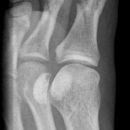

D1 Grundglied